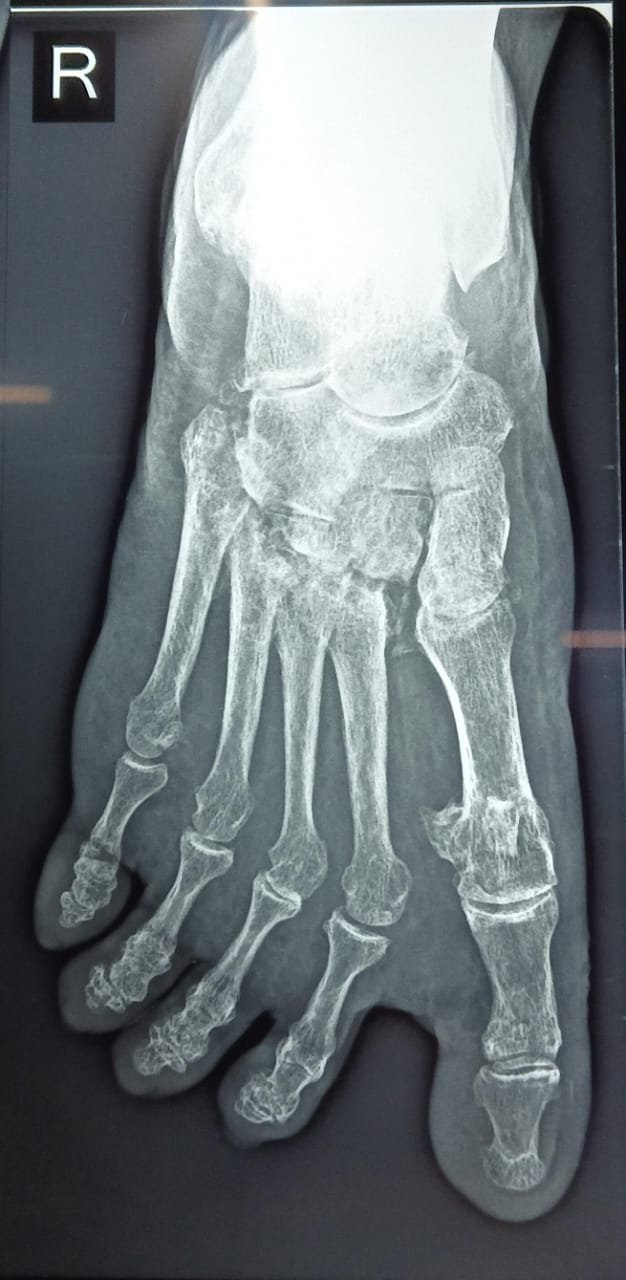

Peri-implant fracture

Open this atlas entry to review structured imaging references.

General Region 2 images 2 months ago